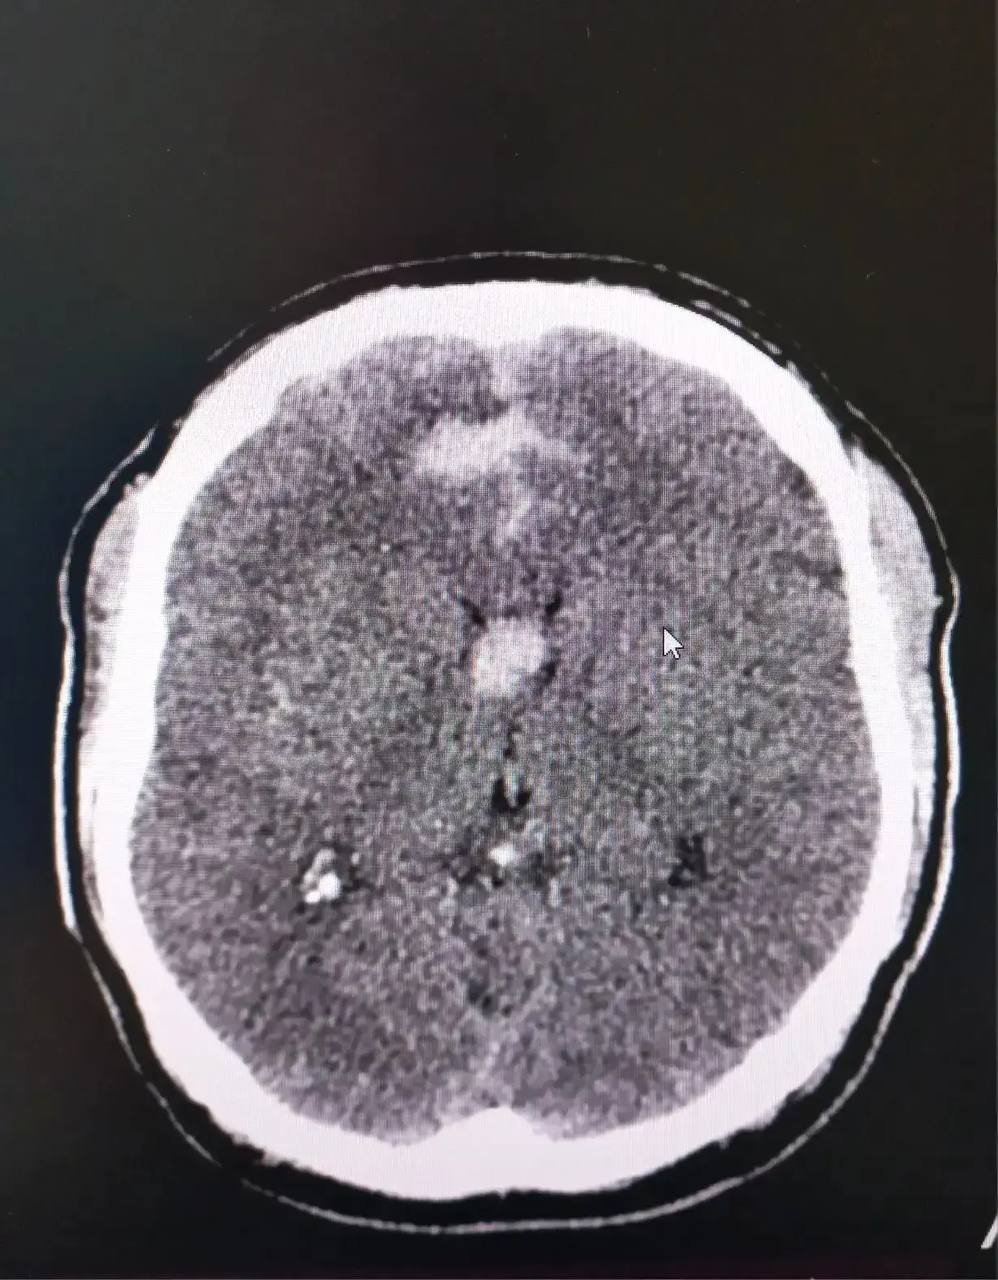

Обследование выявило у пациента врожденную аневризму — опасное изменение кровеносного сосуда. В любой момент он мог разорваться и вызвать кровоизлияние в мозг. Врачи приступили к экстренной операции.

Нейрохирург Михаил Дуболазов и главный специалист Приморья по внутрисосудистой диагностике и лечению Никита Грачев через небольшой прокол в бедренной артерии подвели катетер к сосудам мозга. Врачи установили специальные микроспирали и "закрыли" аневризму, исключив ее из общего кровотока.